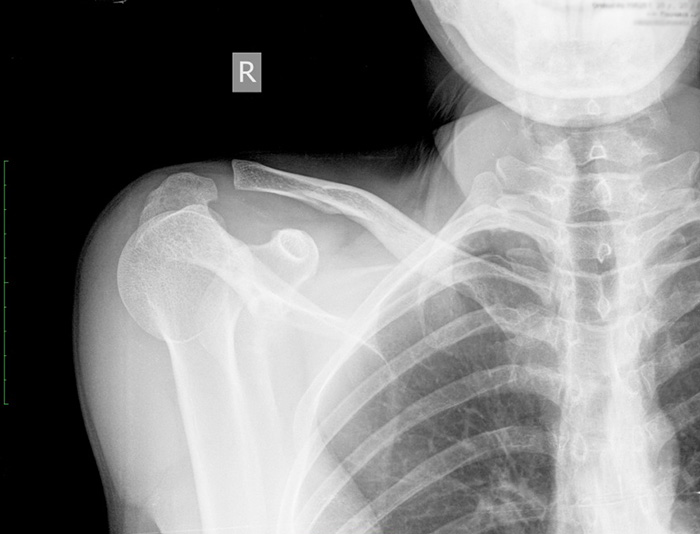

1. Перелом правой ключицы

Причины боли в ключице справа или слева могут связаны переломом кости. Понять, что он произошел помогают признаки:

- возникают сильные, резкие, интенсивные, острые боли в правом плече и в области ключицы, они сохраняются в спокойном положении, становятся ярче при любом движении;

- возникает боль в ключице при вдохе;

- немного облегчить боль в ключице можно, если прижать правую руку к телу и удерживать её левой;

- в области травмы появляется заметный отек, кожные покровы краснеют, становятся горячими на ощупь;

- в некоторых случаях видно, что с костью ключицы справа произошла деформация, её участок стал заметно выпирать над кожей.

Больного требуется доставить в больницу. Смягчить проявления боли можно при помощи болеутоляющих средств (используют Анальгин, Пенталгин). После осмотра хирургом или травматологом назначается рентгенографическое исследование. После изучения его результатов врач соединяет обломки кости правой ключицы, вправляет их и фиксирует в необходимом положении через мягкие ткани. Затем он накладывает гипс или фиксирующую повязку. Если имеются сильные повреждения кожи, мышц, костей, необходима хирургическая операция для их восстановления.

Переломы ключицы

Симптомы перелома сложно спутать с чем-то другим, ведь появляются они преимущественно после травм, о которых пациент помнит: удары, толчки, падения на выпрямленные руки или локти. Боль при переломах очень сильная, отечная, появляются синяки, кость может сменить привычное положение.

Травмы

При переломе имеются внешние признаки — асимметрия обеих ключиц, деформация кожи над местом травмы

Перелом ключицы практически всегда вызывает внешнюю деформацию кости, так как она одна из наиболее тонких в составе скелетного аппарата человека. К тому же ключица окружена сильными мышцами, спазм которых при травме приводит к сдвигу костных отломков. В месте перелома чувствуется острая болезненность, ткани вокруг него опухают с каждым часом всё больше. При надавливании, попытке сделать движение рукой или поднять ее боль усиливается. Если отломок кости сдавливает 3 или 4 позвонок, появляются такие симптомы, как онемение за ухом, «отяжеление» языка, комок в горле.

Вывих ключичной кости также сопровождается ее смещением, отеком и болью при движении. Человек не способен пошевелить плечом, высоко поднять, низко опустить или отвести в сторону руку. При нажатии ключица может встать на место, однако ее положение неустойчиво.